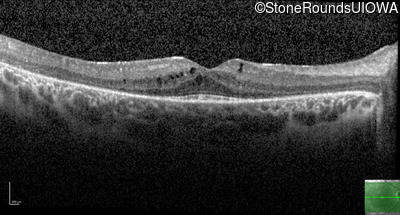

Age at visit: 7 years

OD OS

This 7 year old girl has had very poor vision in dim light and slightly subnormal acuity her entire life.